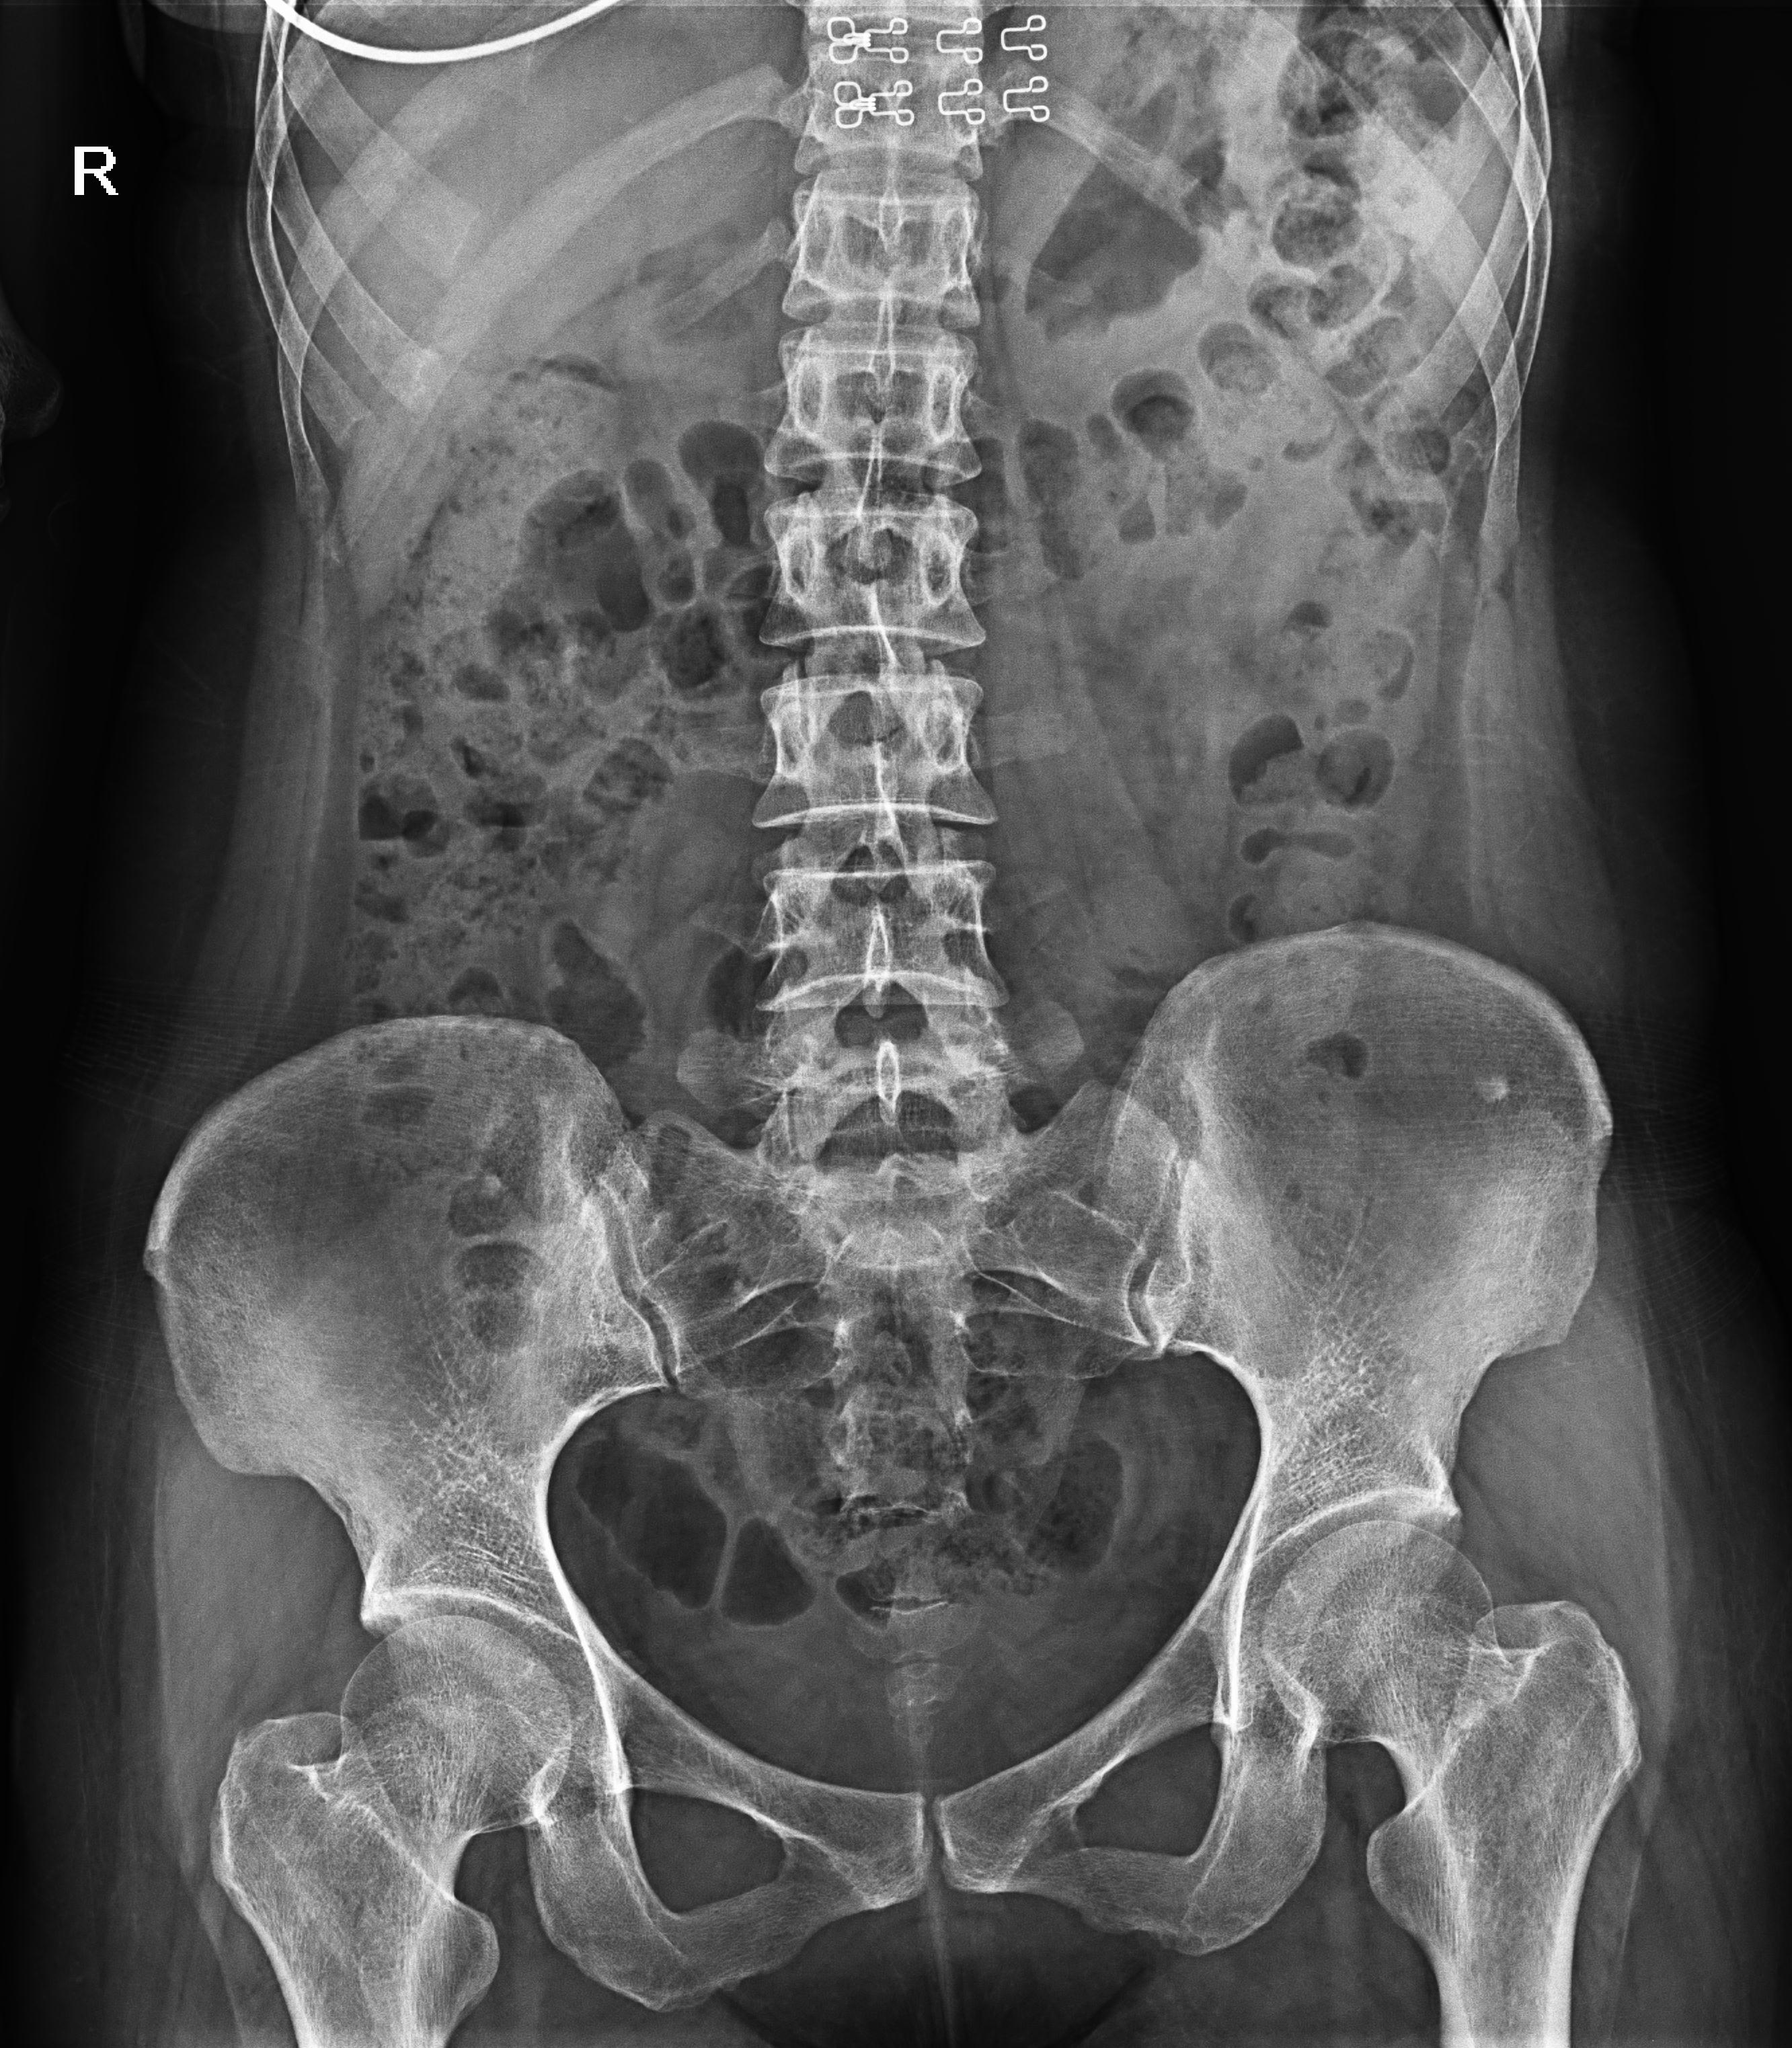

普利德醫療自主研發(fā)的新一代數字化X線(xiàn)透視攝影系統,可應用于DR攝影、數字透視、數字造影以及可視化精準DR拍片等多種臨床X線(xiàn)檢查領(lǐng)域。

● 17*17英寸的超高清像素動(dòng)態(tài)平板探測器,更大的視野范圍,無(wú)需移動(dòng)即可觀(guān)察整個(gè)動(dòng)態(tài)過(guò)程,避免拖尾、噪聲對圖像的影響;

● 高效動(dòng)態(tài)平板技術(shù),圖像不會(huì )有幾何畸變,提供高分辨率和精確的圖像,為醫生臨床診斷提供精準依據;

球管傾斜攝影角度-45°~45°,滿(mǎn)足臨床各部位各角度的攝影需求。如:髕骨軸位、頸椎正位、骶尾椎、鼻竇瓦氏位、梅氏位等部位檢查。

點(diǎn)片裝置移動(dòng)范圍大,無(wú)需患者移動(dòng)就能完成全身各部位的檢查;